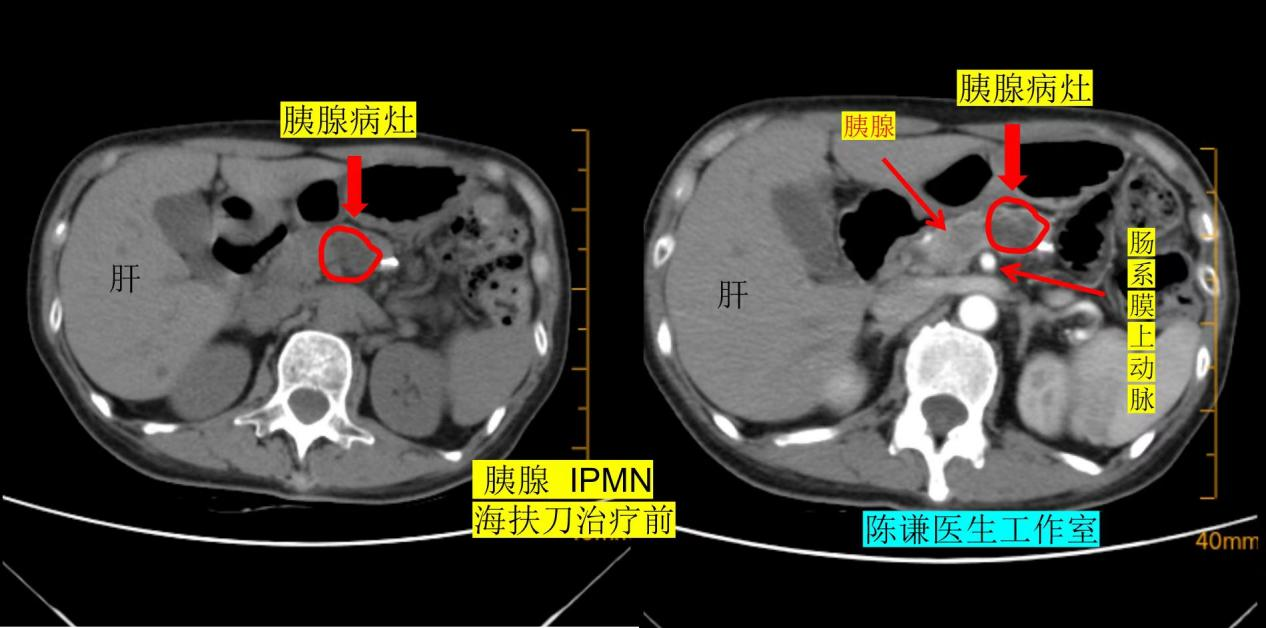

其实,IPMN 是一种起源于胰腺导管上皮的肿瘤性病变,以导管扩张、上皮乳头状增生和黏液分泌为特征,虽多为良性或低度恶性,但部分类型存在恶变风险,且随着病灶增大,恶变概率会逐渐升高。张先生的病灶已出现 “逐渐增大” 的趋势,当地医院给出了明确建议:尽快手术切除。

如今,距离海扶刀进行治疗已过去 4 个月,张先生复查时的结果让医患双方都倍感欣慰:术前 2.4 厘米的胰腺 IPMN 病灶,已缩小至 1 厘米左右,体积足足缩小了 80% ,且肿瘤标志物水平恢复正常,生活质量与治疗前毫无差别。